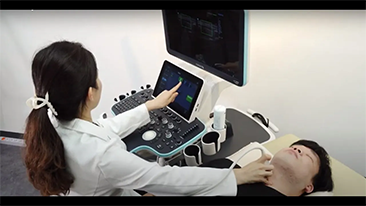

Le soluzioni Mindray Resona per la diagnostica per immagini generale consentono ai medici di ottenere diagnosi e trattamenti con risultati pi├╣ precisi ed efficaci grazie a sonde specifiche complete e a efficienti strumenti clinici applicativi.

L'ambiente medico odierno ├© diventato pi├╣ complesso, con un numero crescente di casi difficili e notevoli carichi di lavoro.